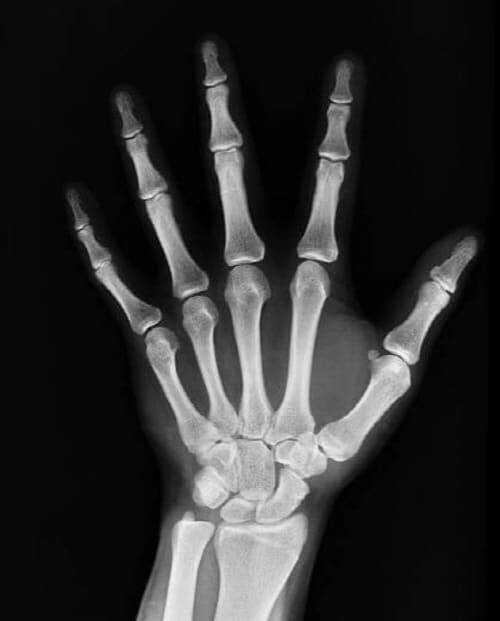

손가락 등의 뼈가 더 빨리 붙고 고관절이나 허벅지, 다리 등은 더 오래 걸리는 것으로 알려져 있습니다.